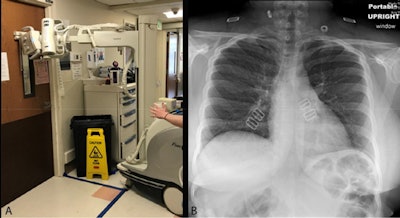

- Use portable equipment and acquire x-rays through glass or at a distance.

Chest radiography through glass. Technologists position the portable x-ray unit outside the patient room, with the tube peering through the wire-reinforced isolation room window (A). The anteroposterior chest x-ray obtained is of diagnostic quality (B). Images courtesy of the RSNA."[We hope] the processes that have been implemented at the University of Washington in managing the COVID-19 pandemic as well as in preparing for patient surges ... may provide important guidance for other radiology departments who are in the early stages of preparation and management," the group wrote.